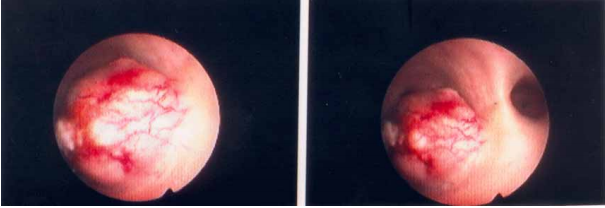

71 68 歲男性病人罹患惡性腫瘤,主訴骨頭疼痛。圖為本次就診之腰椎 X 光攝影。最可能的骨轉移來源 為何?

(A) thyroid cancer (B) adrenal cancer (C) renal cancer (D) prostate cancer